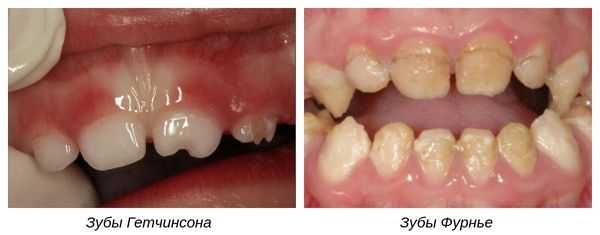

Отдельно рассматривают формы системной гипоплазии, которые затрагивают дентин:

- Зубы Гетчинсона — аномалия, при которой коронки центральных верхних резцов имеют отвёрткообразную форму с полулунными вырезками по режущим краям [9] .

- Зубы Фурнье — зубы бочковидной формы без полулунной вырезки, шейки которых больше режущих краёв.

- Зубы Пфлюгера — аномалия первых моляров (жевательных зубов). Возникает в результате сифилитической инфекции [7] . Зубы имеют конусовидную форму, их бугры недоразвиты, шейки больше жевательной поверхности.

- Зубы Гетчинсона. При данной патологии верхние центральные резцы имеют отверткообразную или бочкообразную форму. Их размер у шейки несколько больше, чем у режущей поверхности и имеется полулунная выемка у режущего края. Ранее полагалось, что данный симптом наблюдается только при врожденном сифилисе, однако позже установили, что аномалия возникает и при иных причинах.

- Зубы Пфлюгера. При данном симптоме поражены первые моляры, размер коронки у щеки больше, чем у жевательной поверхности. Бугры недоразвиты, что придает зубам схожесть с конусом.

- Зубы Фурнье. Клинически выглядят так же, как и при симптоме Гетчисона, но без полулунной выемки.